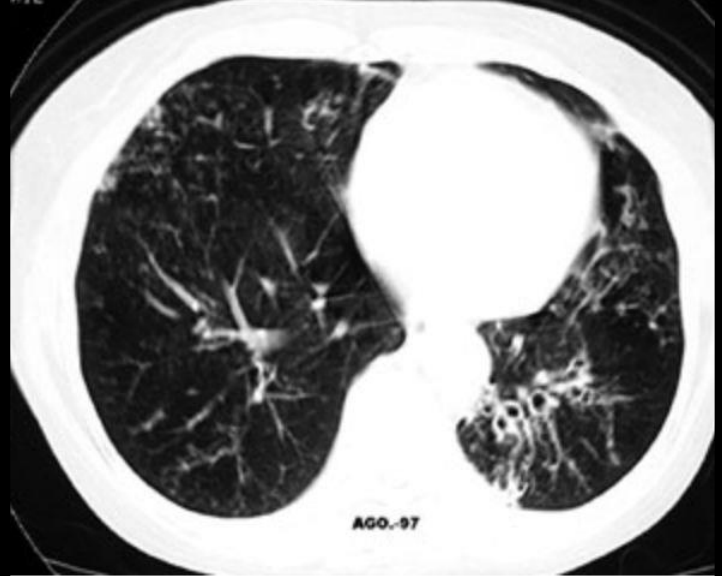

Q

TC

Engrosamiento bronquial e hiperclaridad

SOLO PARA ENF: asociadas (aspergilosis o neumonías)